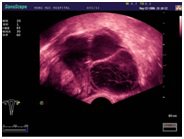

Ультразвуковые исследования, доплеровское сканирование сосудов в Медицинском центре «АКВА МЕД МАРИН» выполняется при помощи первого и единственного аппарата в Керчи SonoScape S40Exp (экспертного класса, который оснащен множеством новейших функций, многократно улучшающих качество и информативность УЗИ-исследования).

В Медицинском центре «АКВА МЕД МАРИН» при помощи профессиональной аппаратуры, проводится: